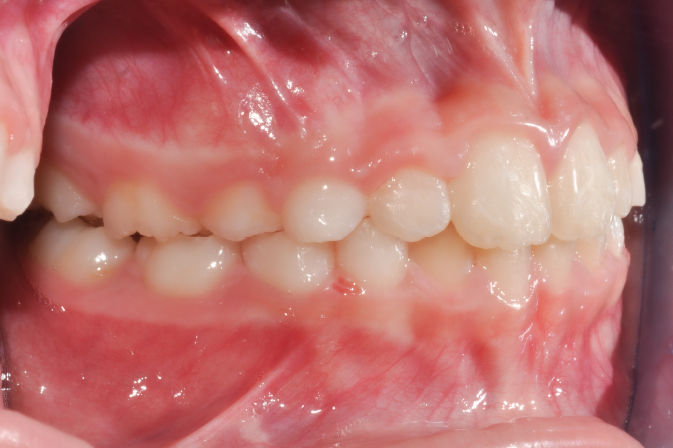

The patient presented with a skeletal Class I relationship and a mesofacial growth pattern, indicating balanced sagittal and vertical skeletal proportions. Dental examination revealed a Class I molar and canine relationship bilaterally. The patient was in the mixed dentition phase. Significant dental crowding was observed in both arches, consistent with a dentoalveolar discrepancy. Midline deviations were present, affecting dental symmetry and occlusal harmony. The maxillary lateral incisors were in crossbite, contributing to anterior transverse discrepancy and functional imbalance.

Periodontal evaluation revealed early signs of periodontal disease, primarily affecting tooth 41. Radiographic assessment demonstrated root convergence of teeth 11 and 21, indicating compromised root parallelism. Overall, the initial presentation was characterized by dentoalveolar crowding, transverse discrepancies, occlusal asymmetries, and early periodontal involvement within an otherwise favorable skeletal framework, requiring a carefully planned orthodontic approach to ensure functional stability and periodontal preservation.